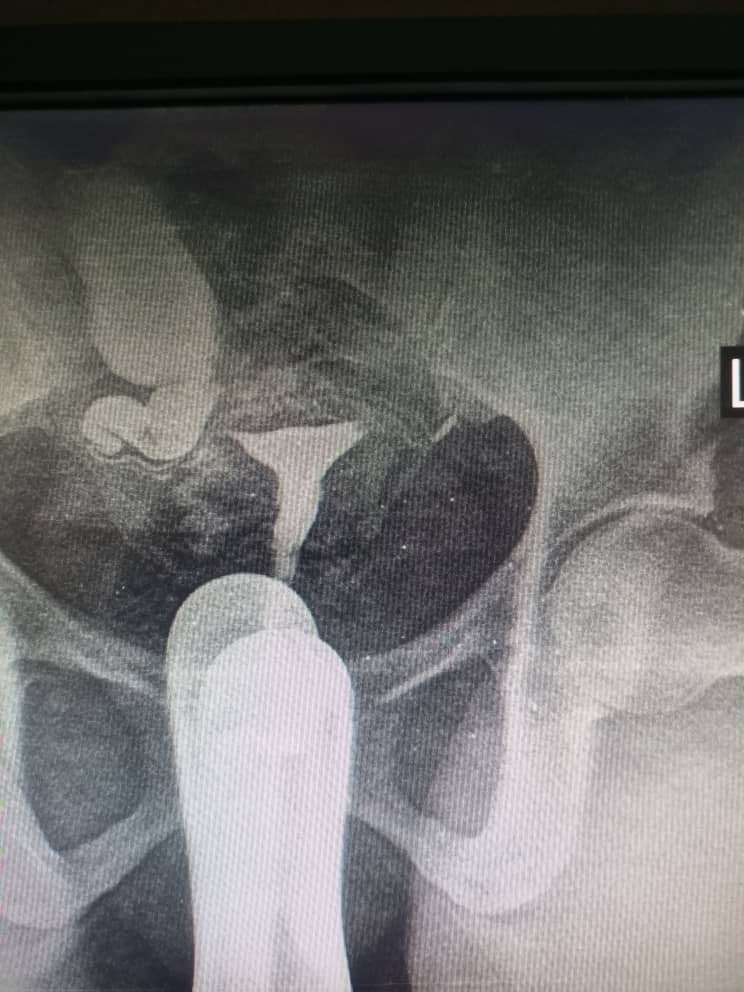

Figure 3: shows bilateral proximal tubal occlusion

The prevalence of tubal pathologies in this study was 29.7% with bilateral proximal tubal occlusion being the most common abnormality, accounting for 10% of cases. This finding corroborates studies conducted in Lagos20 and Oghara21, where similar patterns were reported. However, a study in Zaria22 found unilateral tubal occlusion to be more common. Among unilateral cases, right sided blockages (5.7%) were more prevalent than left sided (2.6%), consistent with findings in Sokoto15 and Lagos20. Conversely, studies in Maiduguri16 and Korle-Bu14 reported left sided predominance. Some cases of bilateral proximal tubal occlusion were presumably due to tubal spasm; in this study all patients had intramuscular injection of hyoscine bromide (Buscopan) at the beginning of the procedure which is thought to prevent spastic tubal occlusion.